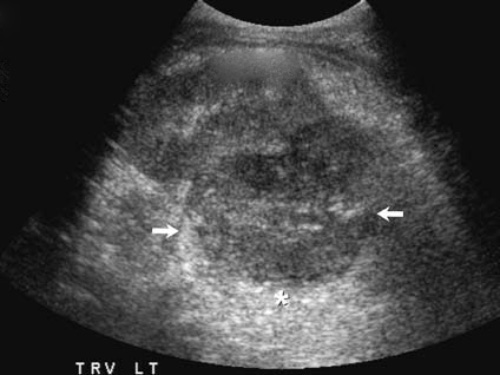

Рисунок 6. Гипоэхогенные тени (стрелки), которые возникают вследствие отклонения волны, вследствие чего ослабленные ультразвуковые волны попадают на изображение тканей данного участка